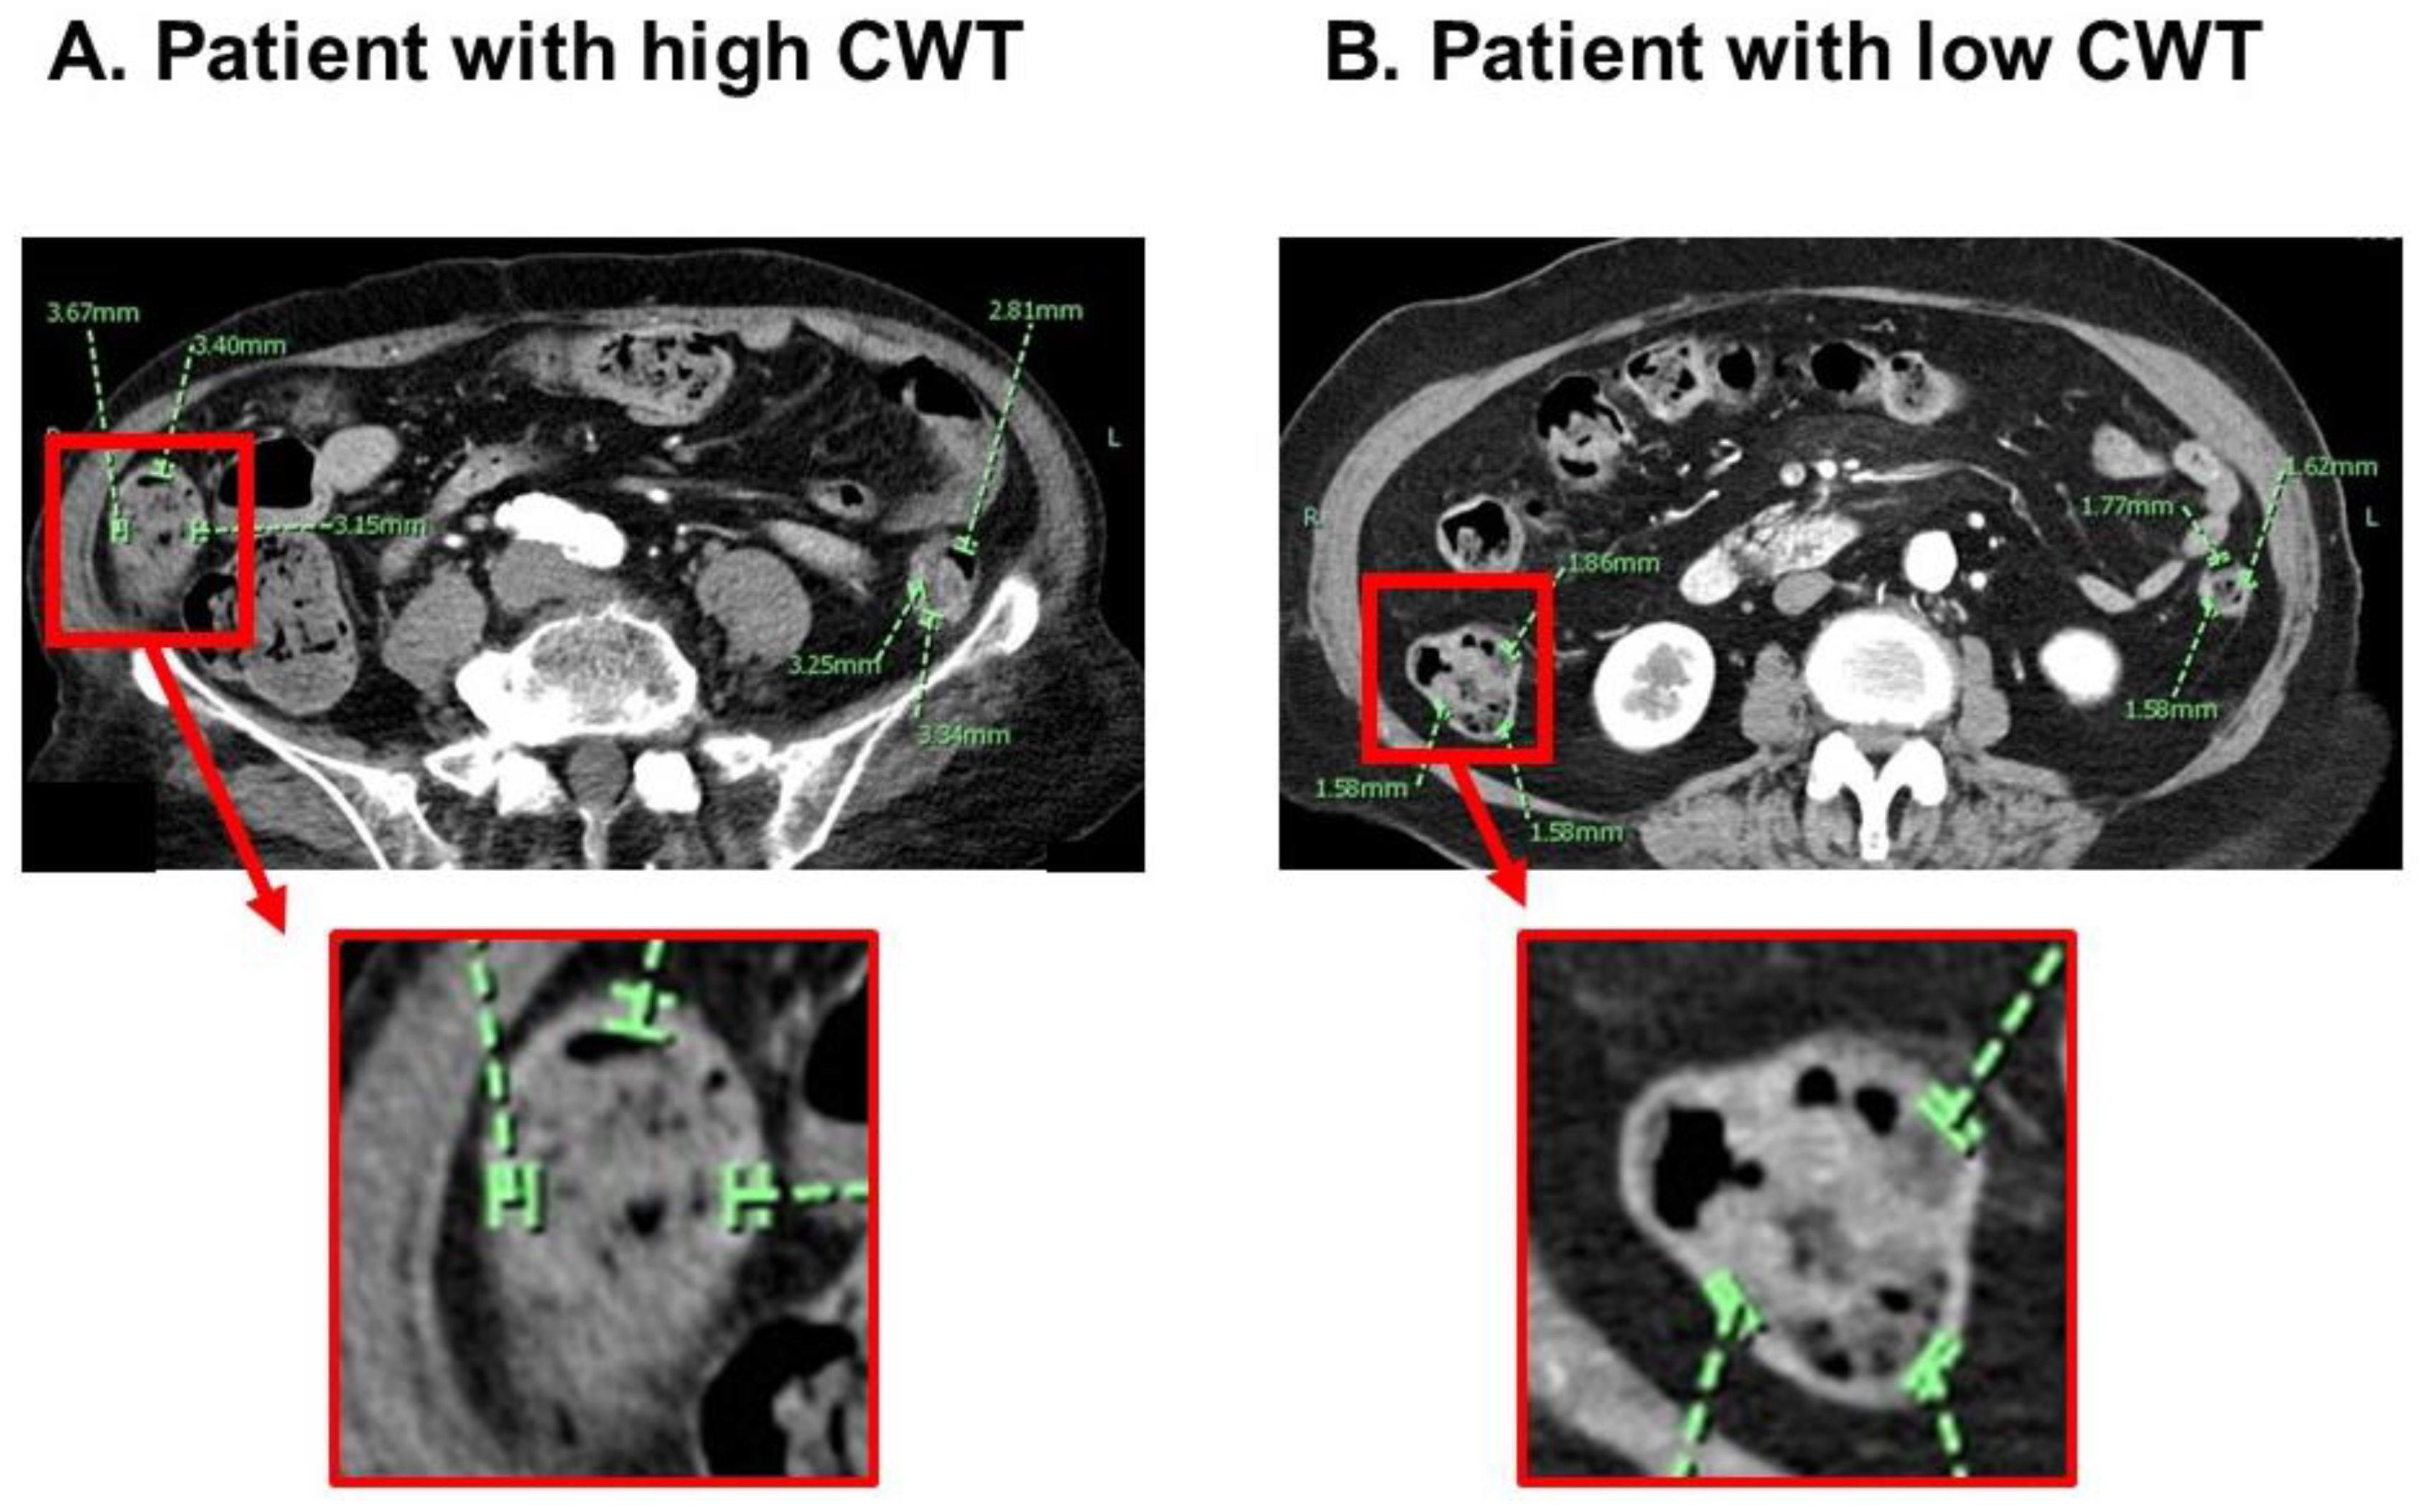

2.2. Measurement of CWT